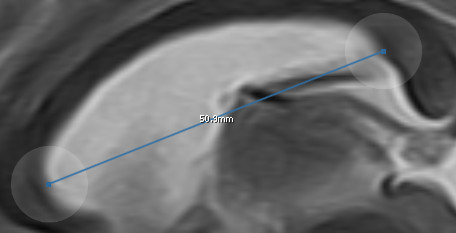

11.1.4. Measurements

The measurement tool ![]() allows you to create measurements on an image slice.

The display length is rounded to one digit after the comma. The inserted measurement can be adjusted by 'Pinch-to-Zoom'.

Alternatively you can adjust booth ends separately.

In order to do so you have to tap on the transparent circles at the end of the line.

You can create as much measurements as you want in one image.

You can reselect a measurement by tapping on it or selecting it from the 'List of annotation' window.

allows you to create measurements on an image slice.

The display length is rounded to one digit after the comma. The inserted measurement can be adjusted by 'Pinch-to-Zoom'.

Alternatively you can adjust booth ends separately.

In order to do so you have to tap on the transparent circles at the end of the line.

You can create as much measurements as you want in one image.

You can reselect a measurement by tapping on it or selecting it from the 'List of annotation' window.